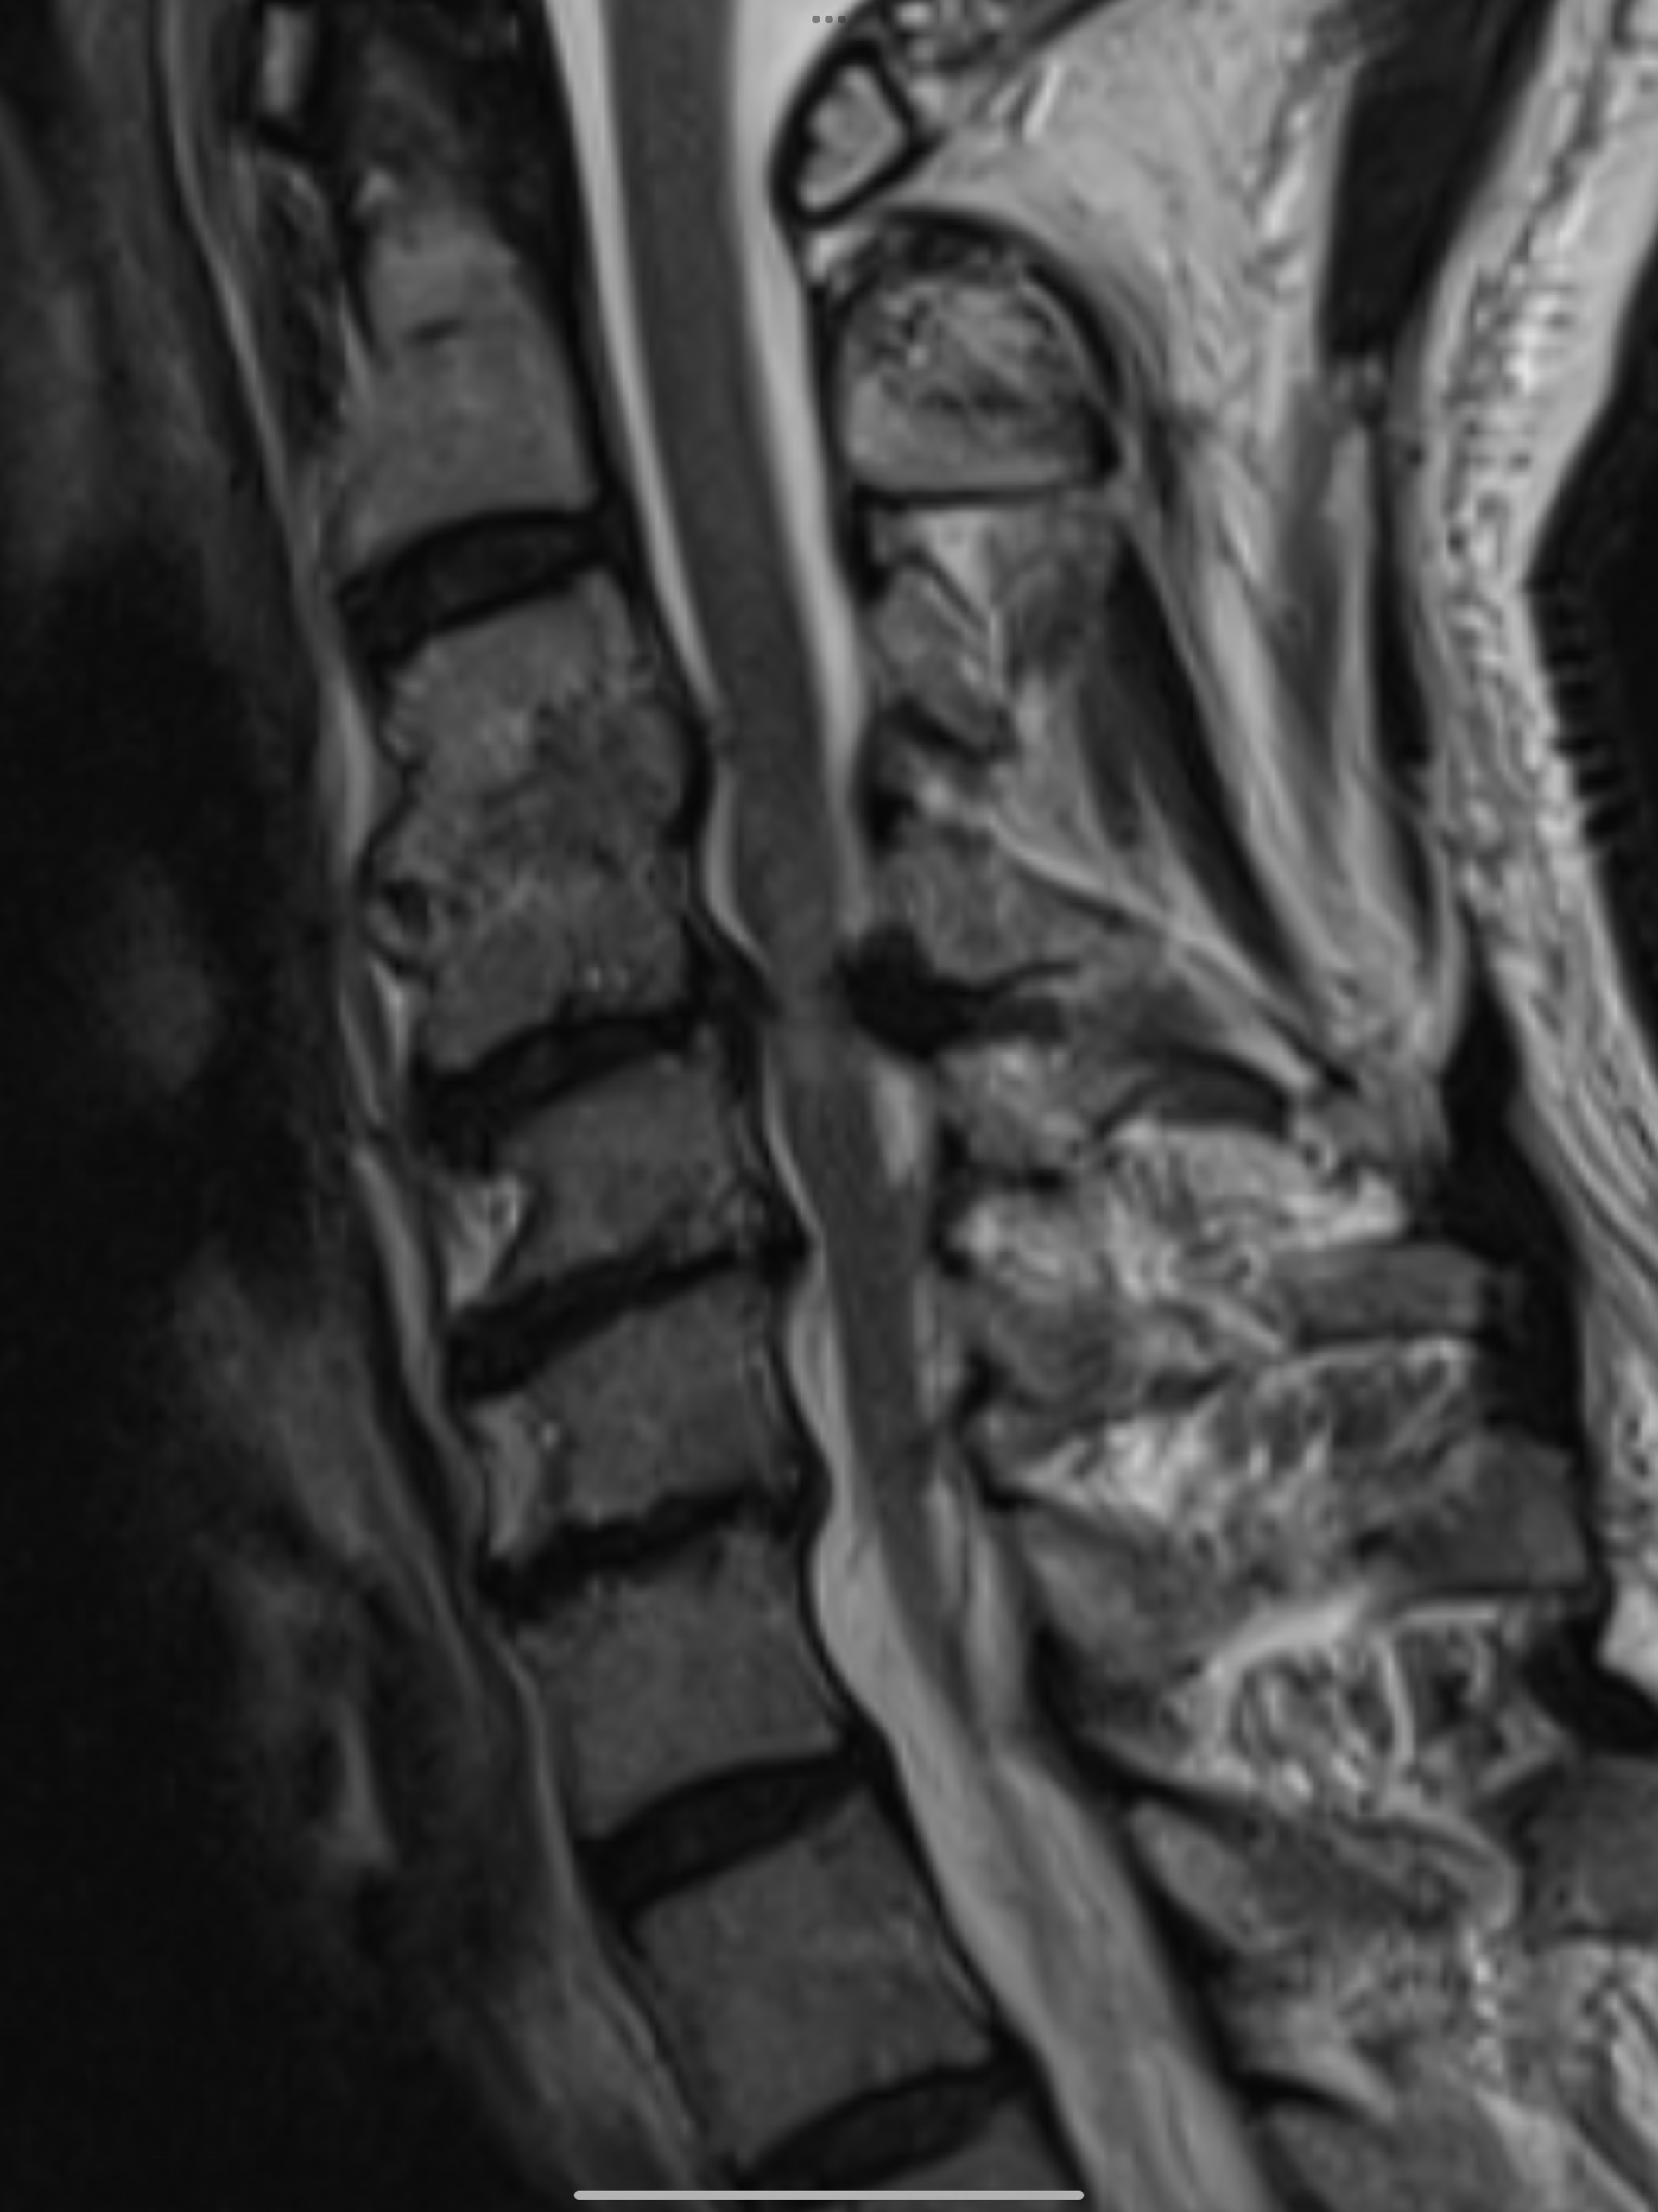

การวินิจฉัยอาการหมอนรองกระดูกคอเสื่อมเริ่มจากการสอบถามอาการและประวัติการเจ็บป่วยของคนไข้ ซึ่งแพทย์จะทำการตรวจร่างกายเพื่อประเมินความรุนแรงของอาการ จากนั้นอาจแนะนำให้ทำการตรวจเพิ่มเติม เช่น การทำ MRI เพื่อให้เห็นภาพหมอนรองกระดูกและเส้นประสาทที่เกี่ยวข้องอย่างชัดเจน

หมอนรองกระดูกคอเสื่อม (Cervical Disc Degeneration) คือการเสื่อมสภาพของหมอนรองกระดูกซึ่งเป็นส่วนที่อยู่ระหว่างกระดูกสันหลังส่วนคอ หมอนรองกระดูกทำหน้าที่ในการรองรับแรงกระแทกและช่วยให้คอเคลื่อนไหวได้อย่างอิสระ เมื่อหมอนรองกระดูกเริ่มเสื่อมสภาพจะทำให้การรองรับแรงกระแทกลดลง ส่งผลให้เกิดอาการปวดคอ รวมถึงอาจกดทับเส้นประสาทที่อยู่ใกล้เคียงทำให้เกิดอาการชาตามแขน มือ หรือแม้กระทั่งอ่อนแรงในบางกรณี